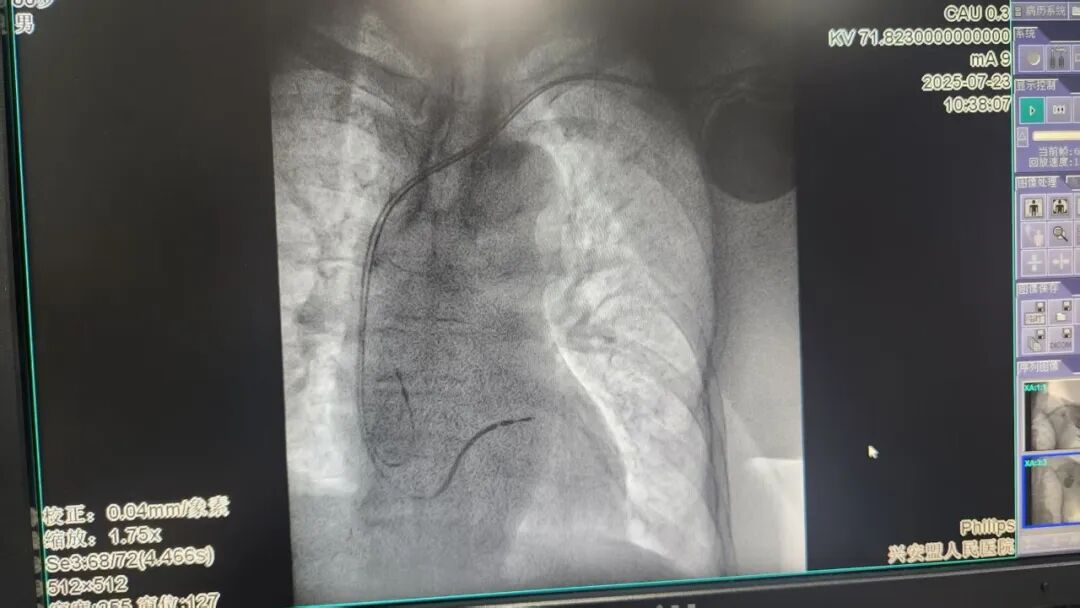

手术由蔡景景主任带领团队实施。在高龄患者血管条件相对较差的情况下,蔡主任克服困难,在局部麻醉下精准操作:成功穿刺血管,将纤细的电极导线分别精准植入患者右心房和右心室的理想位置,并稳妥连接、固定双腔ICD装置。术中,团队一丝不苟地测试设备的感知灵敏度和除颤阈值,确保这台“生命的守护神”能在危急时刻准确、及时地发挥作用。整个手术过程流畅高效,患者顺利康复出院。